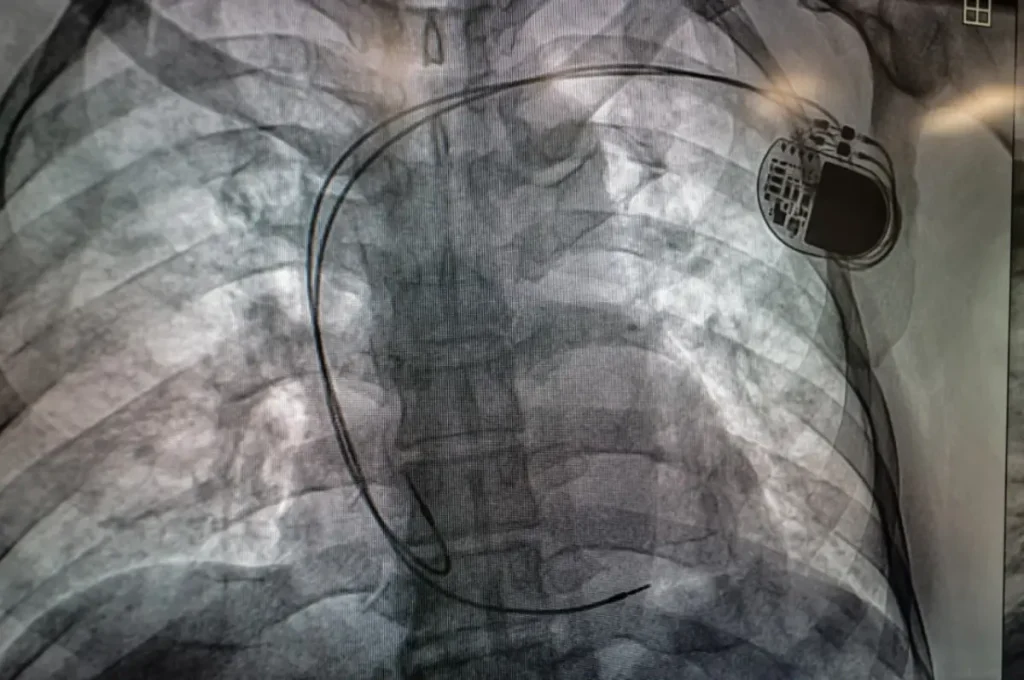

Respecto a la sala de hemodinamia del HRAE de Acapulco, este miércoles se llevó a cabo la primera jornada quirúrgica de colocación de marcapasos, en beneficio de dos derechohabientes de 67 y 93 años, quienes se recuperan favorablemente. Asimismo, mañana se tiene prevista la cirugía de tres cateterismos y dos marcapasos.

El cardiólogo electrofisiólogo a cargo de estas intervenciones, José Salvador Lainez Zelaya, detalló que los pacientes presentaban frecuencias cardíacas muy bajas, por lo que fueron candidatos a la implantación de un marcapasos, procedimiento de mínima invasión que dura aproximada una hora y en la que se utiliza equipamiento, como un fluoroscopio y monitores de alta resolución.

“Terminamos nuestro primer procedimiento de colocación de marcapasos bicameral, en un tiempo de 37 minutos, sin ninguna complicación. El paciente pasa a la Unidad de Cuidados Coronarios y en dos semanas estaremos dándole seguimiento. Este tipo de procedimientos son muy importantes, salvan vidas a pacientes que necesitan estimulación cardíaca”, apuntó.